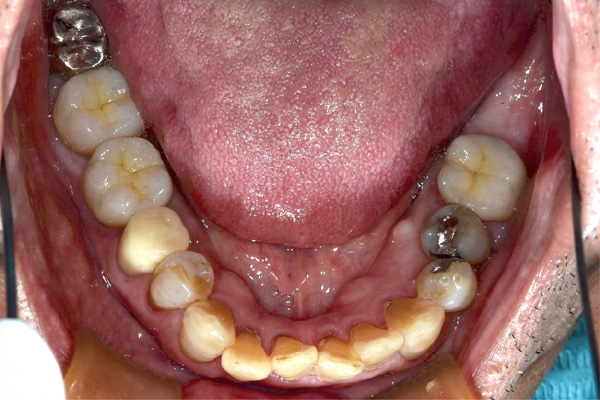

| 年代・性別 | 50代 男性 |

|---|---|

| 主訴 | 右上下の歯が痛い |

| 治療期間 | 約12ヶ月 |

| 費用 | 2,500,000円 |

| 治療内容 | インプラント、骨造成、結合組織移植、セラミック修復 |

| 治療に伴うリスク | インプラント周囲炎 セラミックの破折、脱離 |

*キャンセルポリシーをご一読のうえご予約ください